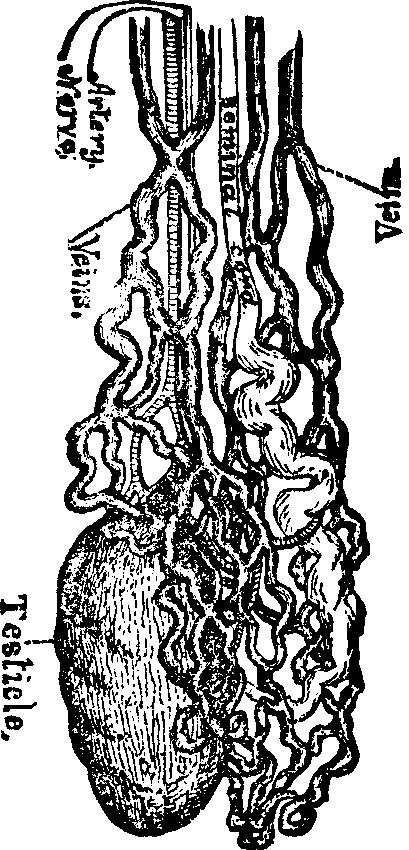

Generation. So long as the vital principle remains in the sperm-cell, it lies dormant. That part of the cell which contains this principle is called the spermatozoön, which consists of a flattened body, having a long appendage tapering to the finest point. If it be remembered that a line is the one-twelfth part of an inch in length, some idea may be formed of the extreme minuteness of the body of a human spermatozoön, when we state that it is from 1/800 to 1/600 part of a line, and the filiform tail 1/50 of a line, in length. This life-atom, which can be discerned only with a powerful magnifying glass, is perfectly transparent, and moves about by executing a vibratile motion with its long appendage. Within this speck of matter are hidden the multifarious forces which, under certain favorable conditions, result in organization. Magnify this infinitesimal atom a thousand times, and no congeries of formative powers is perceived wherewith to work out the wonders of its existence. Yet it contains the principle, which is the contribution on the part of the male toward the generation of a new being.

Fig. 1. A. Human

Spermatozoön magnified about 3,800 diameters. B. Vertical and

lateral views of spermatozoa of man. C, D, E, F. Development of

spermatozoa within the vesicles of evolution. G. Cell of the sponge

resembling a spermatozoön. H. Vesicles of evolution from the

seminal fluid of the dog in the parent cell I. Single vesicles of

different sizes. J. Human spermatozoön forming in its cell.

K. Rupture of the cell and escape of the spermatozoön.